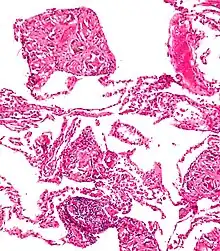

- A coin seen on AP CXR in the esophagus

- A coin seen on lateral CXR in the esophagus

- AP X ray showing a 9mm battery in the intestines

- Lateral X ray showing a 9mm battery in the intestines

- Multiple button batteries in the stomach